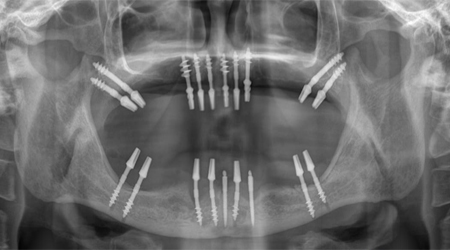

Dental Implant Packages (Lower Jaw)

Technique INR US

8 implants + 14 units Metal-free bridge (Zirconia) 350000 5400

8 implants + 14 units Ceramic bridge (Porcelain fused to metal) 300,000 4500

Dental Implant Packages (Upper Jaw)

10-12 implants including 2 Pterygoid implants + 14 units Metal-free bridge (ZIRCONIA) 400,000 6200

10 implants including 2 Pterygoid implants + 14 units Ceramic bridge (Porcelain fused to metal) 350,000 5500

ALL- ON -4 FOR LESS BONE

Upper Jaw/Lower Jaw (Per Jaw)

4 NOBEL BIOCARE Implants including 2 ANGULATED Implants + IMMEDIATE Provisional Denture + Final Fixed Titanium Hybrid Denture of 12-14 Teeth 350000 5400

4 NOBEL BIOCARE Implants including 2 ANGULATED Implants + IMMEDIATE Provisional Denture + Final Fixed PROCERA Implant Bridge Denture of 12-14 ZIRCONIA Ceramic Crown 500000 7600

ALL- ON -4 WITH ZYGOMA IMPLANTS (FOR MINIMAL BONE)

Upper Jaw

4 NOBEL BIOCARE Implants including 2 ZYGOMA Implants + IMMEDIATE Provisional Denture + Final Fixed TITANIUM HYBRID Denture of 12-14 Teeth 650000 10000

4 NOBEL BIOCARE Implants (QUAD ZYGOMA)+ IMMEDIATE Provisional Denture + Final Fixed TITANIUM HYBRID Denture of 12-14 Teeth 800000 12300